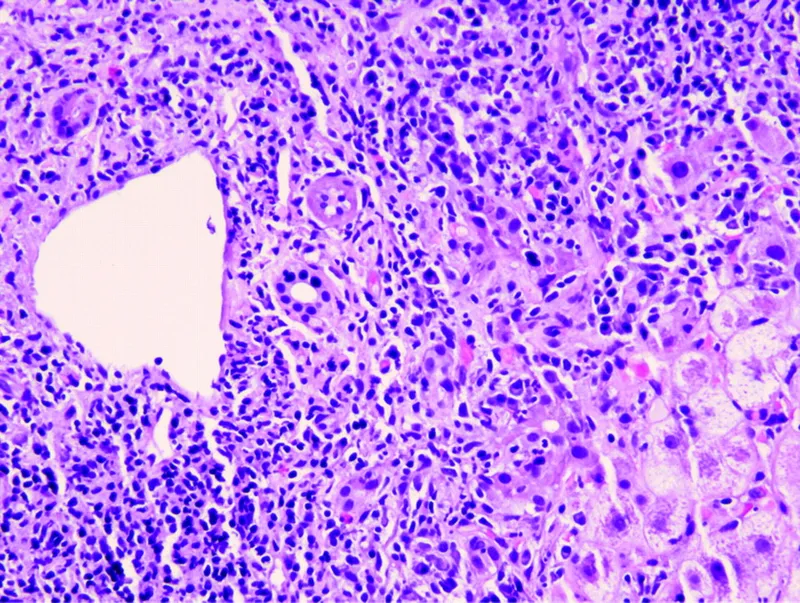

- Hepatocellular: Direct hepatocyte damage.

- Hepatocellular Necrosis (Direct & Idiosyncratic):

- Acetaminophen (dose-dependent), NSAIDs, Statins

- Isoniazid, Halothane, Valproate, Phenytoin